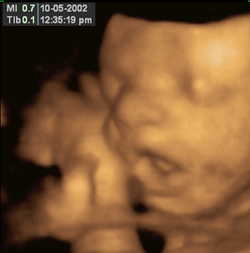

3D Ultrasound

Sept 23, 2000